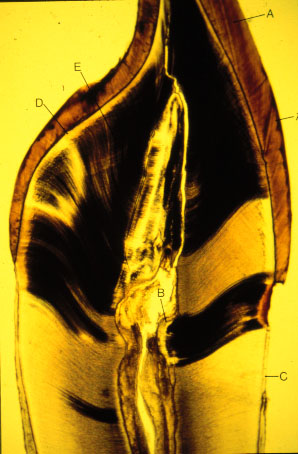

K-slide 68: Higher magnification of slide 67

A. Striae of Retzius

B. Reparative dentin (irregular secondary dentin)

C. Cementum

D. Mantle dentin

E. Circumpulpal dentin